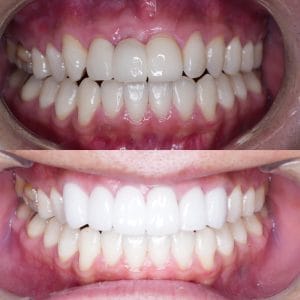

Case029

セラミック矯正の患者様です。

・上下の歯の入れ違い

・正中の歪みと隙間

を主訴にご来院くださいました。

この患者様は若年性歯周炎にかかってしまったため、一生懸命に歯を磨き、口の中は綺麗なのにも関わらず歯茎が下がってしまい、隙間が出来てしまっています。

これは矯正治療で歯の並び方を変えても絶対に無くなりません。

そのため、患者様の主訴を叶えるためにセラミック矯正で治療計画を練りました。

前のクリニックでは「上下一本ずつ抜糸してブリッジで矯正する」という計画だったようですが、

・患者様が非抜歯を希望されていること

・歯を抜かなくても綺麗に並べられそうだったこと

を理由に、当院では上は抜かずにセラミック。下は形態修正だけで対応しました。

この方針変更だけでもお値段も安く、また侵襲(ダメージ)を少なくすることができました。

治療の結果、最低限の侵襲で、見違えるほど綺麗な口元に治療することができ、患者様もとても喜んでくださいました。

主訴とご希望によって、ワイヤー矯正、マウスピース矯正、セラミック矯正のどの矯正が適しているかは異なります。

当院では上記全ての治療法に対応することができるので、主訴とご希望に沿った方法で治療することが可能です。

カウンセリングにてご希望をお伺いした後、一つ一つの治療の違い、当院のおすすめをご紹介いたしますので、ご希望の治療方法をお選びいただけます。

歯並びなどお口元にお悩みのある方、より綺麗な口元になりたい方はぜひ一度ご相談ください。

【主訴】

・上下で入れ違っている前から2本目の歯のすれ違いを治したい。

・清潔感のある白さで明るい綺麗な口元にしたい

・歯の隙間を無くしたい

【ご要望、ご状況】

・歯を抜かずに治したい

・前医では上下1本ずつ抜歯をして、ブリッジで上3本、下3本の計6本を治すことを提案された。

【今回の治療法】

・右上の犬歯から左の前歯までの計4本をジルコニアセラミックで治療

・色は自分の歯よりやや白いくらいでホワイトニングをしてもしなくても大丈夫なくらいの白さ

・歯は抜かない

・右下の歯は形態修正だけで対応

・歯茎のラインを歯肉整形術で整える